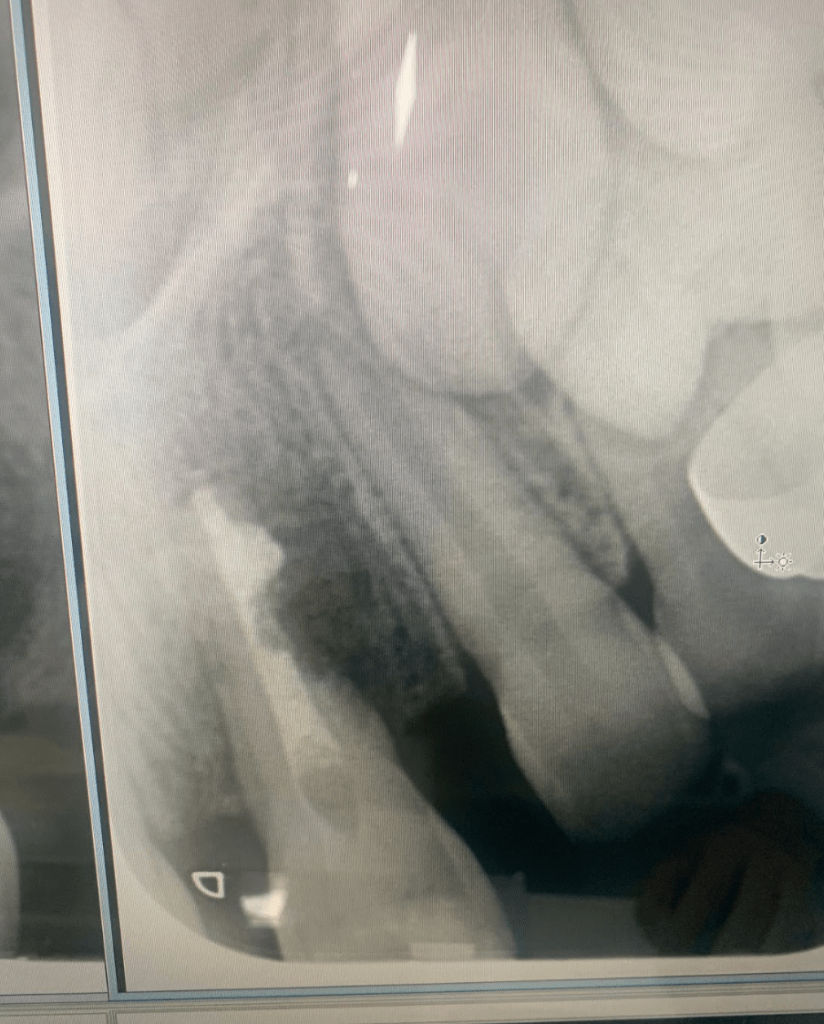

Fractura con exposición pulgar

Reconstrucción con recubrimiento pulgar indirecto